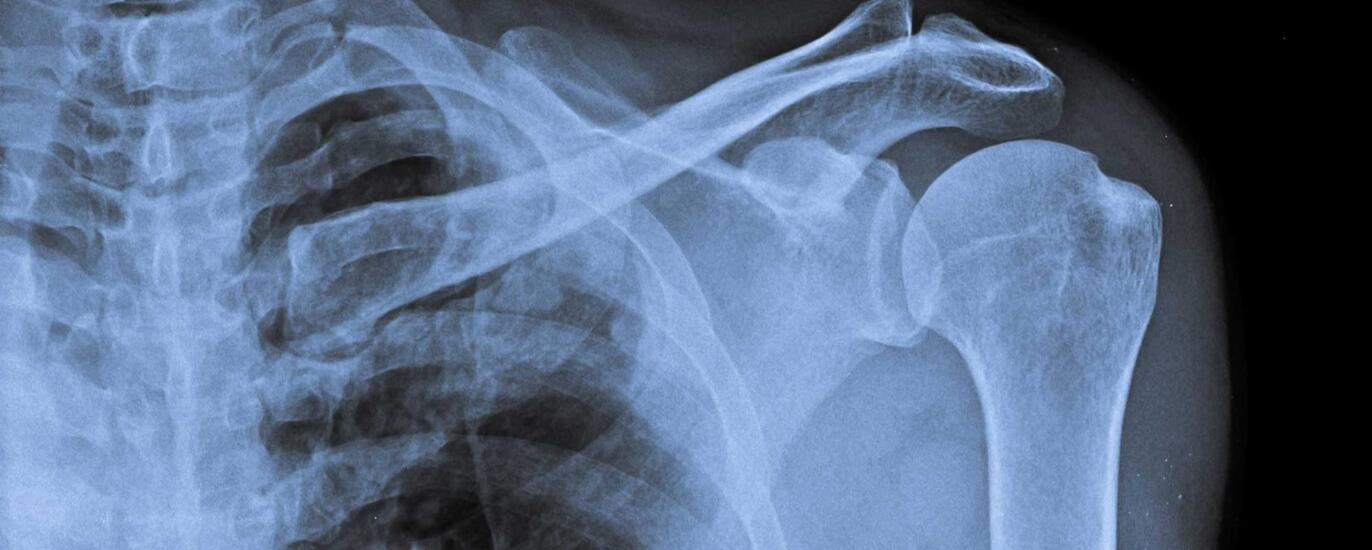

Das Schultergelenk

Es verbindet den Oberarm mit dem Schulterblatt und gilt als Kugelgelenk: das Schultergelenk. Es ist das beweglichste unserer Gelenke. Dies kommt daher, dass es vor allem durch die Muskulatur gestützt wird. Seine Bewegungen werden kaum durch knöcherne Strukturen eingeschränkt. Diese Anatomie macht das Schultergelenk aber auch anfällig für Verletzungen. So kommen Ausrenkungen – sogenannte Luxationen — der Schulter relativ oft vor. Weitere mögliche Verletzungen sind Muskel- oder Sehnenrisse.